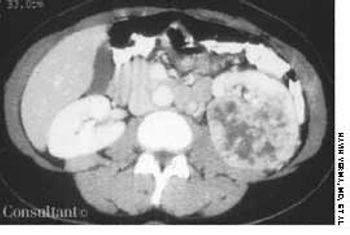

A 43-year-old woman was admitted to the hospital withleft flank pain. The physical examination revealed a left abdominalmass. Laboratory test results identified normochromic-normocytic anemia (hematocrit, 33%; hemoglobin,10.8 g/dL; and mean corpuscular volume, 88 fL) andmicroscopic hematuria (10 red blood cells per high-powerfield).